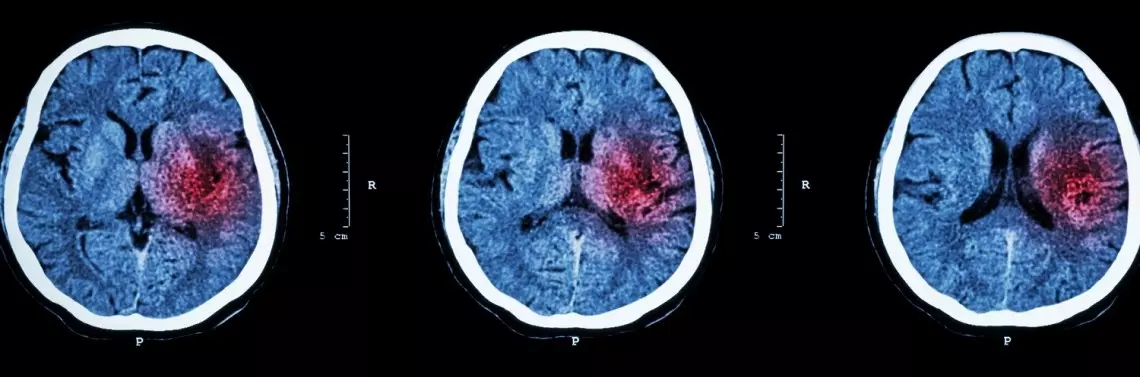

Istotną rolę w diagnostyce udaru niedokrwiennego mózgu odgrywają badania neuroobrazowe. Najważniejsze na początku zachorowania jest ustalenie rodzaju udaru, od tego bowiem zależy dalsze postępowanie diagnostyczne, a przede wszystkim leczenie. Badanie TK ma zasadnicze znaczenie w różnicowaniu udaru niedokrwiennego z udarem krwotocznym. Natomiast badanie MRI uwidacznia nawet małe zawały, również te na podstawie mózgu, w pniu mózgu i innych strukturach tylnego dołu czaszkowego, tj. obszarów nieuwidocznionych w badaniu TK w ciągu pierwszych godzin.